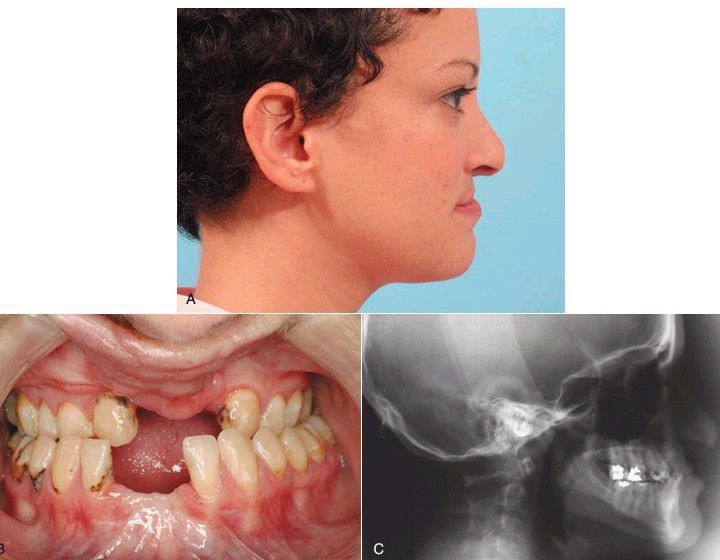

(A) Facial profile of typical patient with a cleft. Note the pseudoprognathic appearance of the mandible. (B) Occlusal relationship showing Angle class III relationship with anterior crossbite. (C) Lateral cephalogram showing maxillary skeletal sagittal deficiency contributing to class III occlusal relationship.